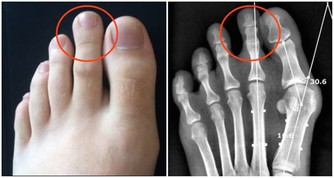

3 、降低腫瘤的發生概率

儘管目前沒有明確的文章提示,肥胖患者患腫瘤的概率一定高,但有研究已經證明,減重後會降低某些激素的分泌,而這些激素,其中有部分就能促進腫瘤的生長。